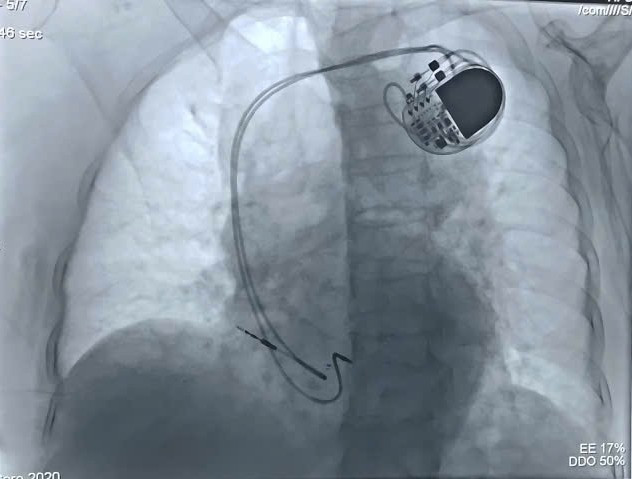

may-tao-nhip-2.jpg

Hình ảnh máy tạo nhịp vĩnh viễn qua phim chụp DSA - Ảnh BVCC